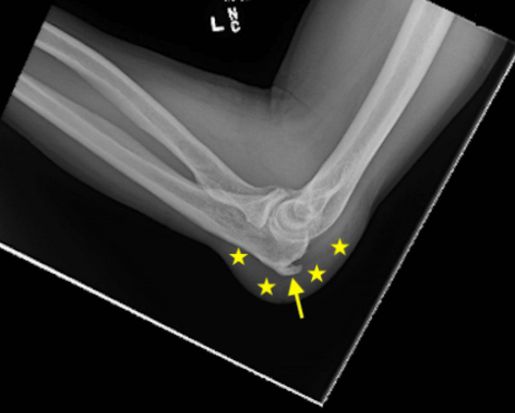

- шпора (костный нарост) локтевого отростка, которая раздражает ткань, покрывающую локоть [4].

![Рентгенограмма со шпорой локтевого отростка (стрелка) и воспаление бурсы, заполненной жидкостью (звёздочки) [7] Рентгенограмма со шпорой локтевого отростка (стрелка) и воспаление бурсы, заполненной жидкостью (звёздочки) [7]](/media/bolezny/bursit-loktevogo-sustava/rentgenogramma-so-shporoy-loktevogo-otrostka-strelka-i-vospalenie-bursy-zapolnennoy-zhidkostyu-zvyozdochki-7_s.jpeg?dummy=1758798960186)

Рентгенограмма со шпорой локтевого отростка (стрелка) и воспаление бурсы, заполненной жидкостью (звёздочки) [7]